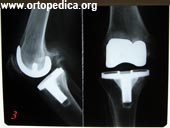

3. Больной Д. Состояние после тотального эндопротезирования левого коленного сустава по поводу остеоартроза 3 ст. Модель De Puy Sigma